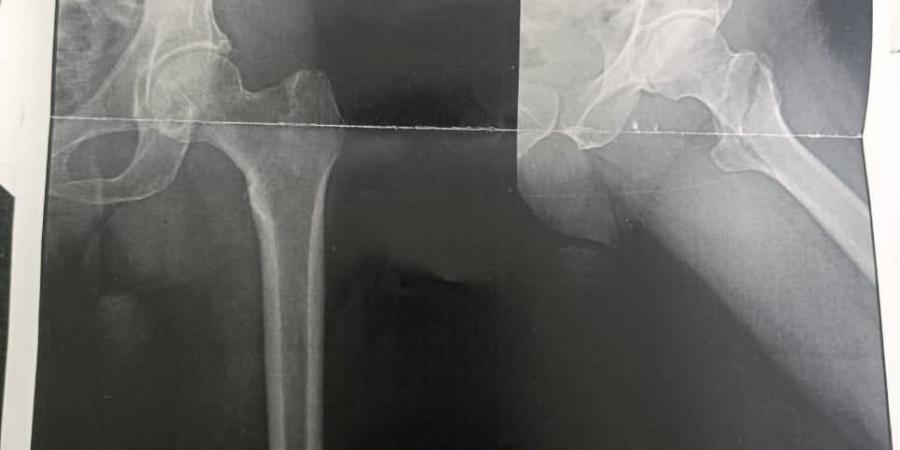

حيث تم إجراء جراحة تغيير نصف مفصل ثنائي القطبين لسيدة تبلغ من العمر 85 عامًا كانت تعاني من كسر بعنق عظمة الفخذ، وخرجت الحالة مستقرة بعد الجراحة.

كما تم إجراء عملية تثبيت كسر بمدور عظمة الفخذ لرجل يبلغ من العمر 75 عامًا باستخدام الشرائح والمسامير، مع تحسن ملحوظ واستقرار الحالة.